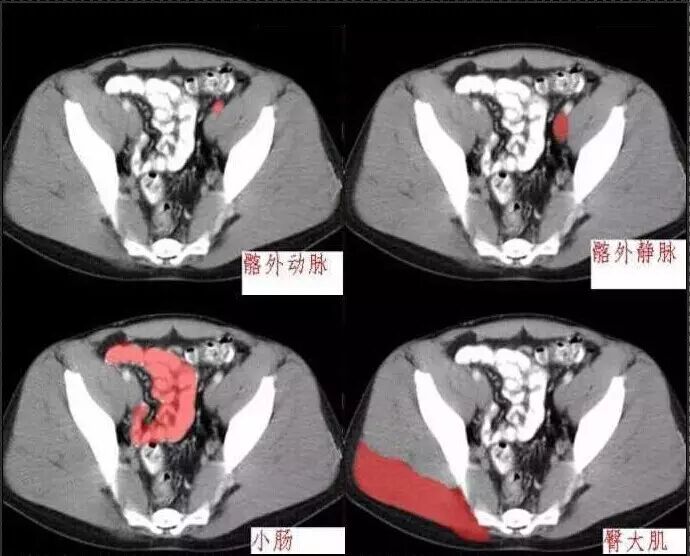

十分钟学会腹部CT解剖(多图)